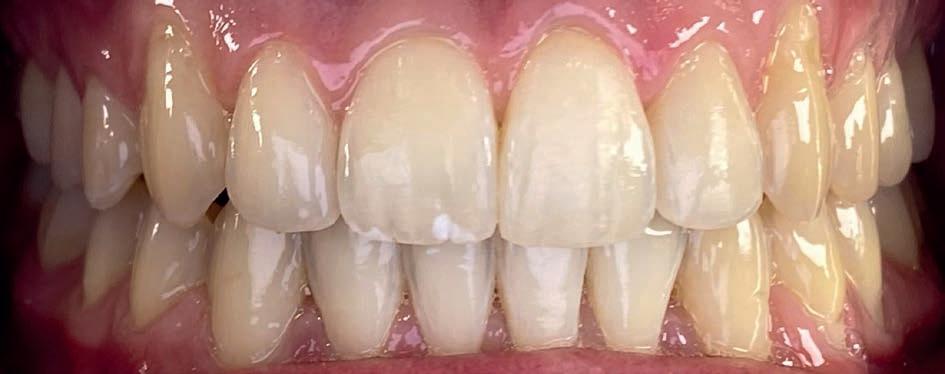

Casus: Blix – Ruimte creëren zonder extracties met D-gainer en Damon Ultima Blix (10 jaar) presenteerde zich met een klasse II-occlusie, smalle boven- en onderkaak en ruimtegebrek voor de doorbraak van de hoektanden en premolaren. Hoewel haar gezicht in balans was, zou zonder behandeling het gebrek aan ruimte toenemen en de diepe beet verder verergeren.

2. Vaste beugel (Damon Ultima)

Na voldoende ruimte werd gestart met de volledige vaste beugel in boven- en onderkaak. Hiermee werden de tandbogen uitgevlakt, de scheefstand gecorrigeerd en de tandbogen verbreed – met behoud van het natuurlijke profiel.

Resultaat

• Klasse I-occlusie

• Harmonieuze lachlijn en verbrede tandbogen

• Geen extracties

• Profiel en gezichtsbalans behouden

Retentie: Vaste spalk boven én onder, aangevuld met een nachtbeugel

“Door ruimte te creëren met een D-gainer in plaats van tanden te trekken, blijft het profiel natuurlijk en ontstaat een bredere, stabiele tandboog.”

voor